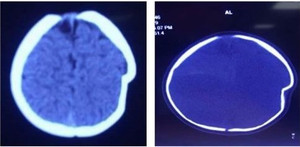

Khi chụp cắt lớp vi tính sọ não và siêu âm phần mềm vùng sưng, bác sĩ chẩn đoán bé trai có ổ tụ máu ngoài màng cứng vùng thái dương - chẩm trái. Bệnh nhi được chuyển đến Bệnh viện Đa khoa Hùng Vương (Phú Thọ) điều trị.

Bệnh nhi có ổ tụ máu ngoài màng cứng vùng thái dương - chẩm trái. (Ảnh: BVCC)